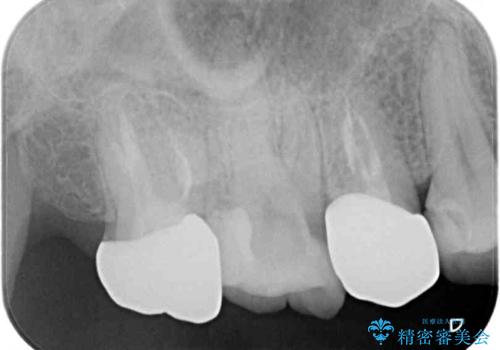

右上の歯は噛んだときに何カ所か痛みを感じるとのことで、診査したところ第二小臼歯が患歯と疑われました。

右上の歯は、第二小臼歯の初回処置後に痛みを感じなくなったため、他の歯については問題なしと診断しました。